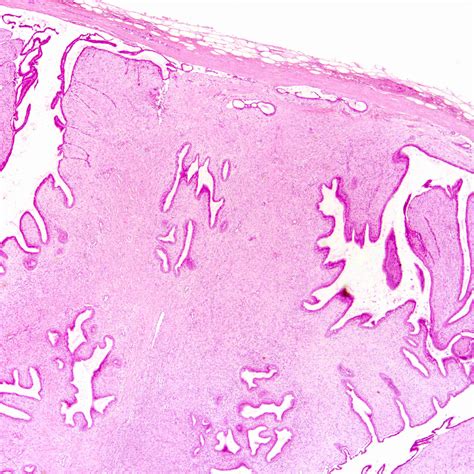

Histopathological Analysis

Histopathological analysis is the gold standard for diagnosing phyllodes tumors. A core needle biopsy or excisional biopsy is performed to obtain a tissue sample for microscopic examination. The histopathological features, including stromal overgrowth, epithelial components, and cellularity, are evaluated to determine the tumor's type and grade.

Benign phyllodes tumors are the most common type, accounting for approximately 60-70% of all phyllodes tumors. These tumors are typically slow-growing and have a low risk of recurrence. They are characterized by a well-defined border and a leaf-like architecture, with stromal overgrowth and epithelial components.